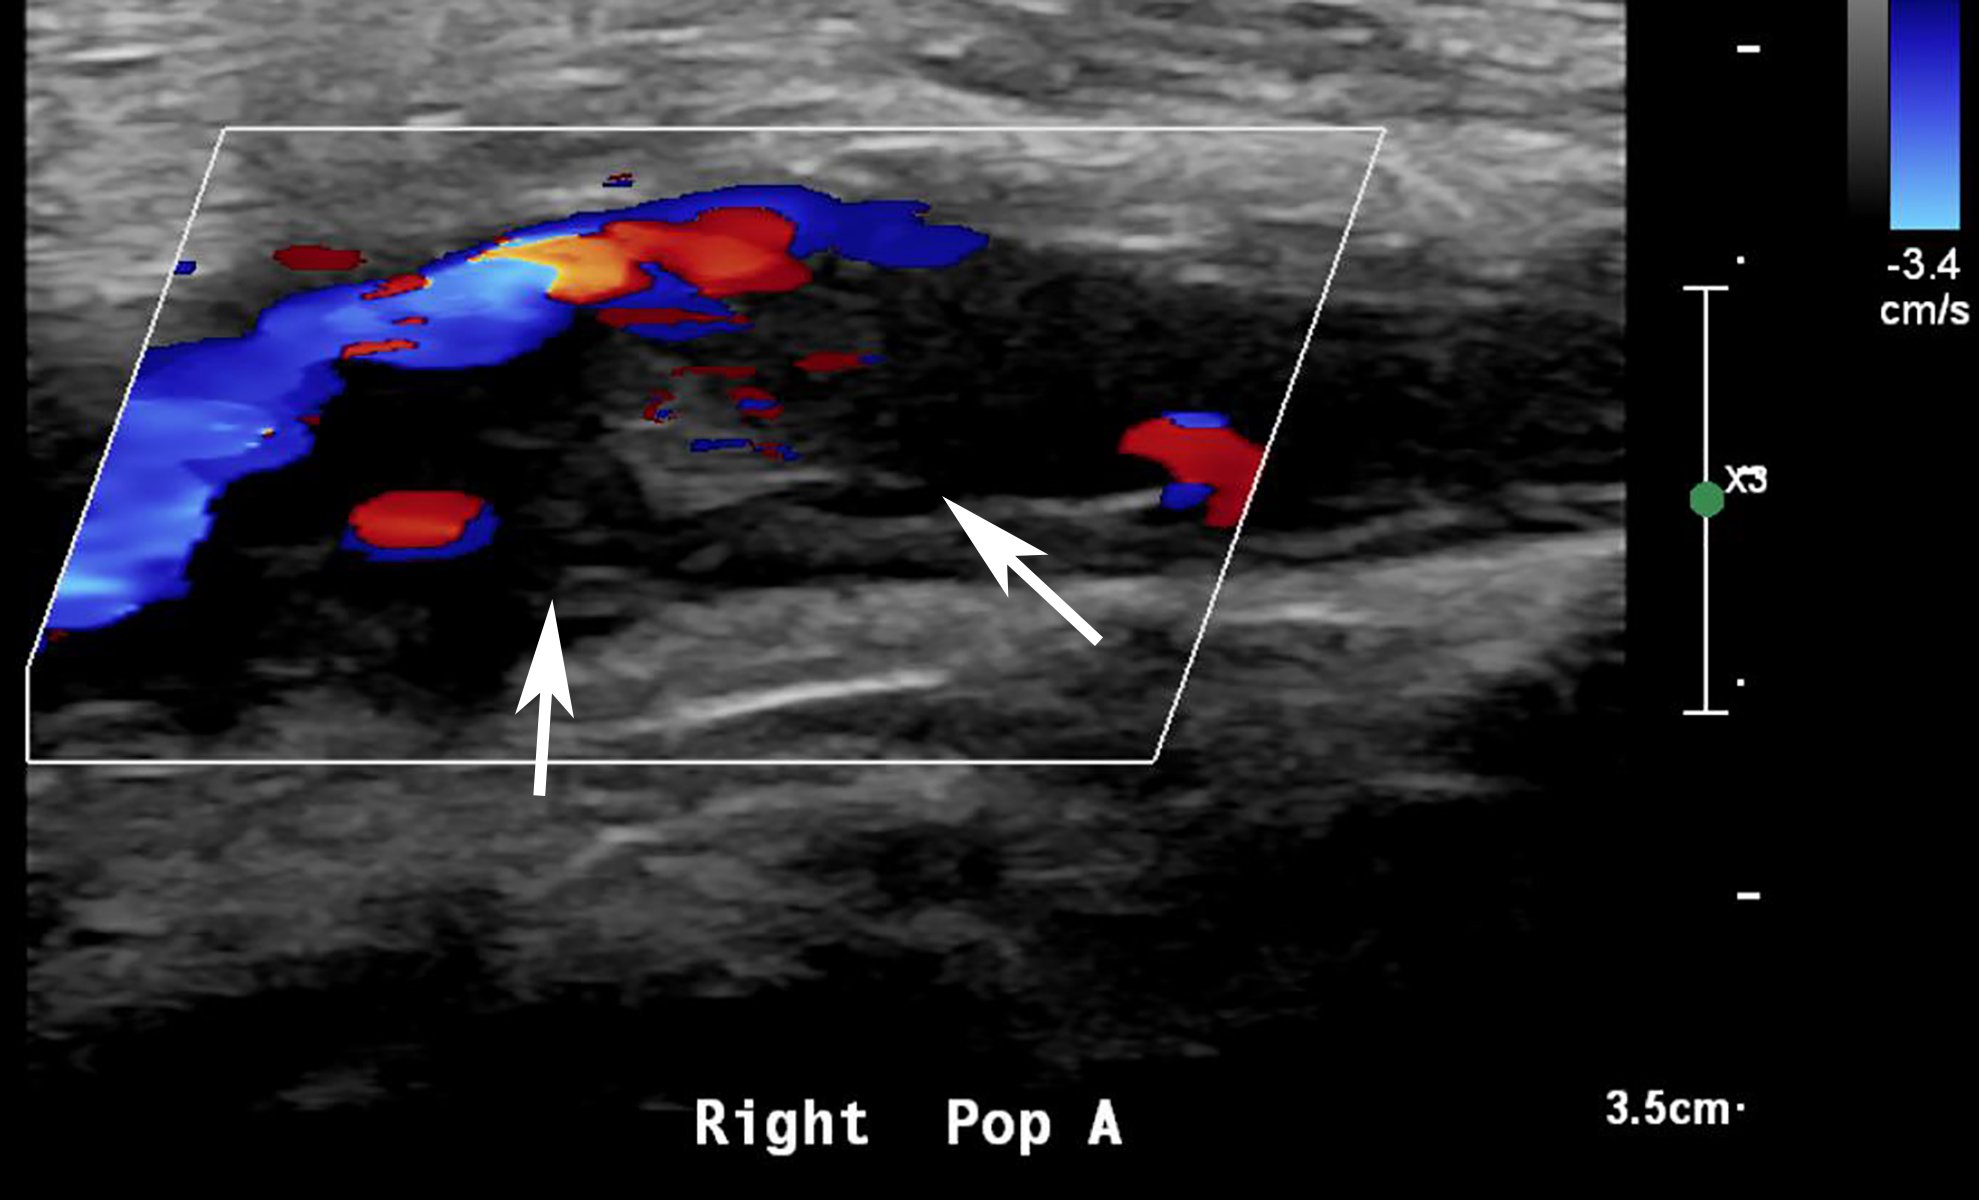

This photo gallery shows the variety of radiological presentations of COVID-19 (SARS-CoV-2) in medical imaging, including computed tomography (CT), radiograph X-rays, ultrasound, echocardiograms and magnetic resonance imaging (MRI). The radiology images show examples of typical COVID pneumonia in the lungs and the numerous complications the virus causes in the body in multiple organs, including the brain, kidneys, heart, abdomen and vascular system.

Ultrasound, especially hand-held ultrasound imaging devices, have become a primary imaging modality for novel coronavirus because of the ease to bag the device and sterilize it after use. CT and mobile X-ray systems are also used as front-line imaging systems for COVID-positive or suspected COVID patients.